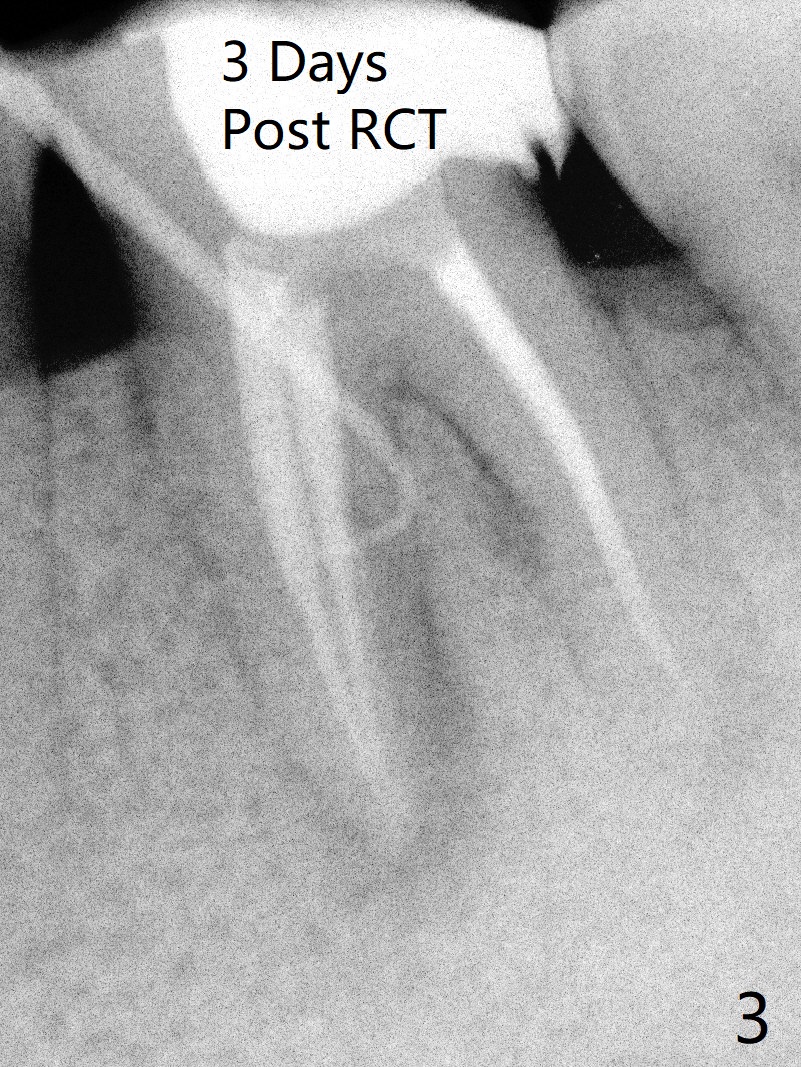

A 29-year-old man has chronic apical perio-dontitis at #19 (Fig.1) for 5 years before RCT with apical buccal swelling (Fig.2). Three days post RCT a fistula develops (Fig.3); curettage is performed. Crown is prepared 3.5 years later (Fig.4). Bitewing is taken immediately before cementation (Fig.5). There is no leakage 2 years 8 months post cementation (Fig.6,7) or periapical radiolucency 6 years 3 months post RCT (Fig.8). Return to Professionals Xin Wei, DDS, PhD, MS 1st edition 11/27/2019, last revision 11/28/2019